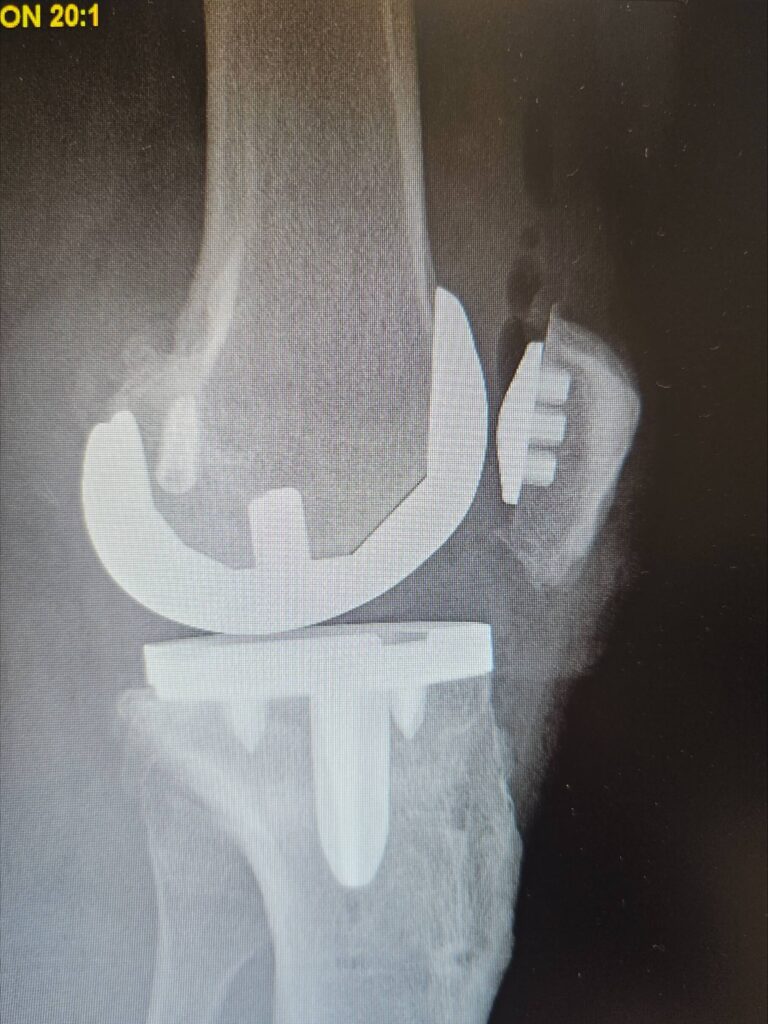

Last week marked a significant milestone in orthopedic surgery as Dr. Jared T. Lee, Medical Director and orthopedic surgeon at The Steadman Clinic in Aspen, Colorado, successfully performed the 5th ever customized press-fit total knee replacement in the United States — a monumental achievement that reflects his commitment to precision, innovation, and patient-centered care.

Traditional total knee replacements typically use standard implants fixed to bone with medical cement. In contrast, press-fit implants are designed to achieve stability through bone ingrowth — allowing the patient’s own bone to integrate with the implant surface over time rather than relying on cement fixation.

A customized press-fit knee goes even further: using advanced imaging (such as MRI or CT scans) taken before surgery, the implant is individually designed to match the exact anatomy of the patient’s knee joint. This tailored fit can improve alignment, preserve more bone, and maximize contact with the surrounding bone structure.

- Better fit, better function: Custom implants that match a patient’s unique anatomy can improve comfort, range of motion, and long-term function.

- Bone-preserving approach: Press-fit techniques can preserve more natural bone and may offer easier revision surgery if needed in the future.